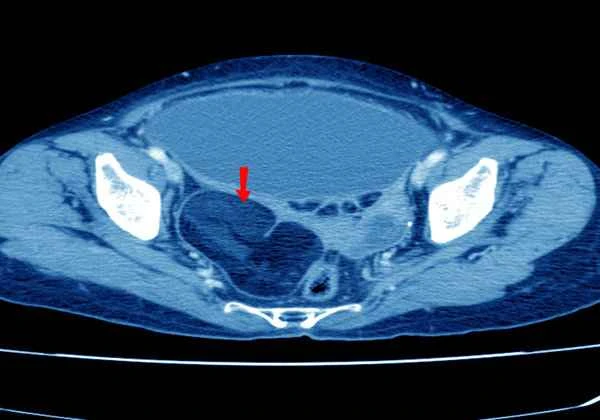

The diagnosis of abdominal adhesions typically involves a medical history, physical examination, and imaging studies. Doctors will determine the extent and degree of adhesions using methods such as abdominal CT, MRI, or laparoscopy, depending on the patient's specific condition. Understanding the principles and practical details of these examination methods helps patients better cooperate with the doctor's diagnostic process.